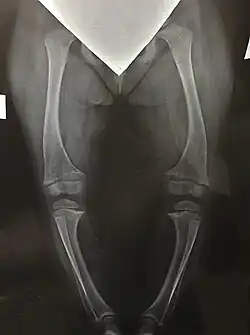

- Рентгенография кистей и костей ног для оценки состояния костной ткани (в зонах метафизов трубчатых костей видны характерные для рахита изменения такие, как неровность края метафиза, вогнутость метафиза с истиранием краев кости, формирование бокаловидных вдавлений, повышение прозрачности зоны метафиза);

Нарушение минерализации костей при Х-ГФР приводит к развитию прогрессирующих деформаций ног у ребёнка. Движения ребёнка становятся тяжелыми и ограниченными, происходит развитие артрозов крупных суставов и деформаций позвоночника. Кроме того, деформации ног ведут к выраженному косметическому дефекту, что может являться причиной для серьёзных переживаний ребёнка по поводу своей внешности.

Возможные типы деформаций ног при Х-ГФР

- О-образная (варусная деформация);

- Х-образная (вальгусная деформация);

- Сочетание Х и О-образной (деформация по типу «дующего ветра»).

При выраженных деформациях нижних конечностей с разрушением структуры тазобедренных и коленных суставов, а также при значительном ограничении активных передвижений показано оперативное лечение. Для этого применяются различные хирургические методики.